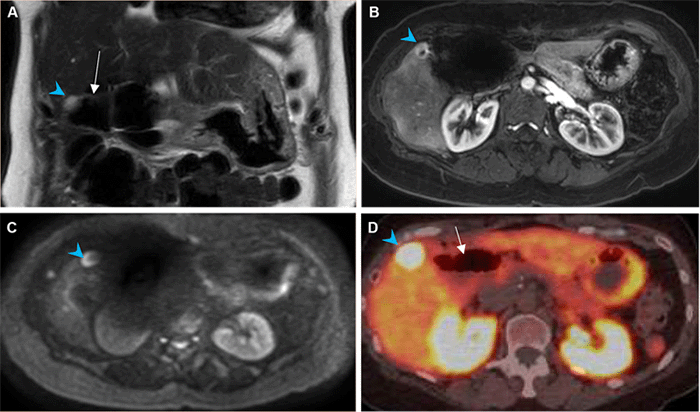

Two weeks after the patient's hospitalization, serum chromogranin A levels were found to be elevated to 1502 ng/mL (reference range <93 ng/mL). Serum gastrin levels were not obtained due to lab error. Subsequent magnetic resonance imaging (MRI) revealed a hypervascular, diffusion-restricting 1.2 cm lesion in liver segment V with focal uptake on gallium-68 (68Ga) DOTATATE positron emission tomography, confirming metastatic recurrence (Figure 2). Four months following this hospitalization, the patient successfully underwent superselective 90Y TARE with microsphere delivery through an arterial branch solely supplying the segment V tumor. There was no evidence of extrahepatic radiotracer uptake on a post-embolization single-photon emission computed tomography (SPECT) scan. She experienced mild fatigue from post-embolization syndrome in the months following the procedure but otherwise recovered well. A repeat MRI showed the segment V treatment zone with minimal peripheral enhancement and no evidence of residual or recurrent disease.

Figure 2. Magnetic Resonance Imaging. Published with Permission

A) Segment V liver lesion (blue arrowhead) hyperintense on T2 and directly adjacent to bowel (white arrow); B) enhancing on arterial phase; C) and with restricted diffusion on diffusion-weighted imaging; D) gallium-68 DOTATATE positron emission tomography/computed tomography demonstrating intense focal uptake (May 2019)